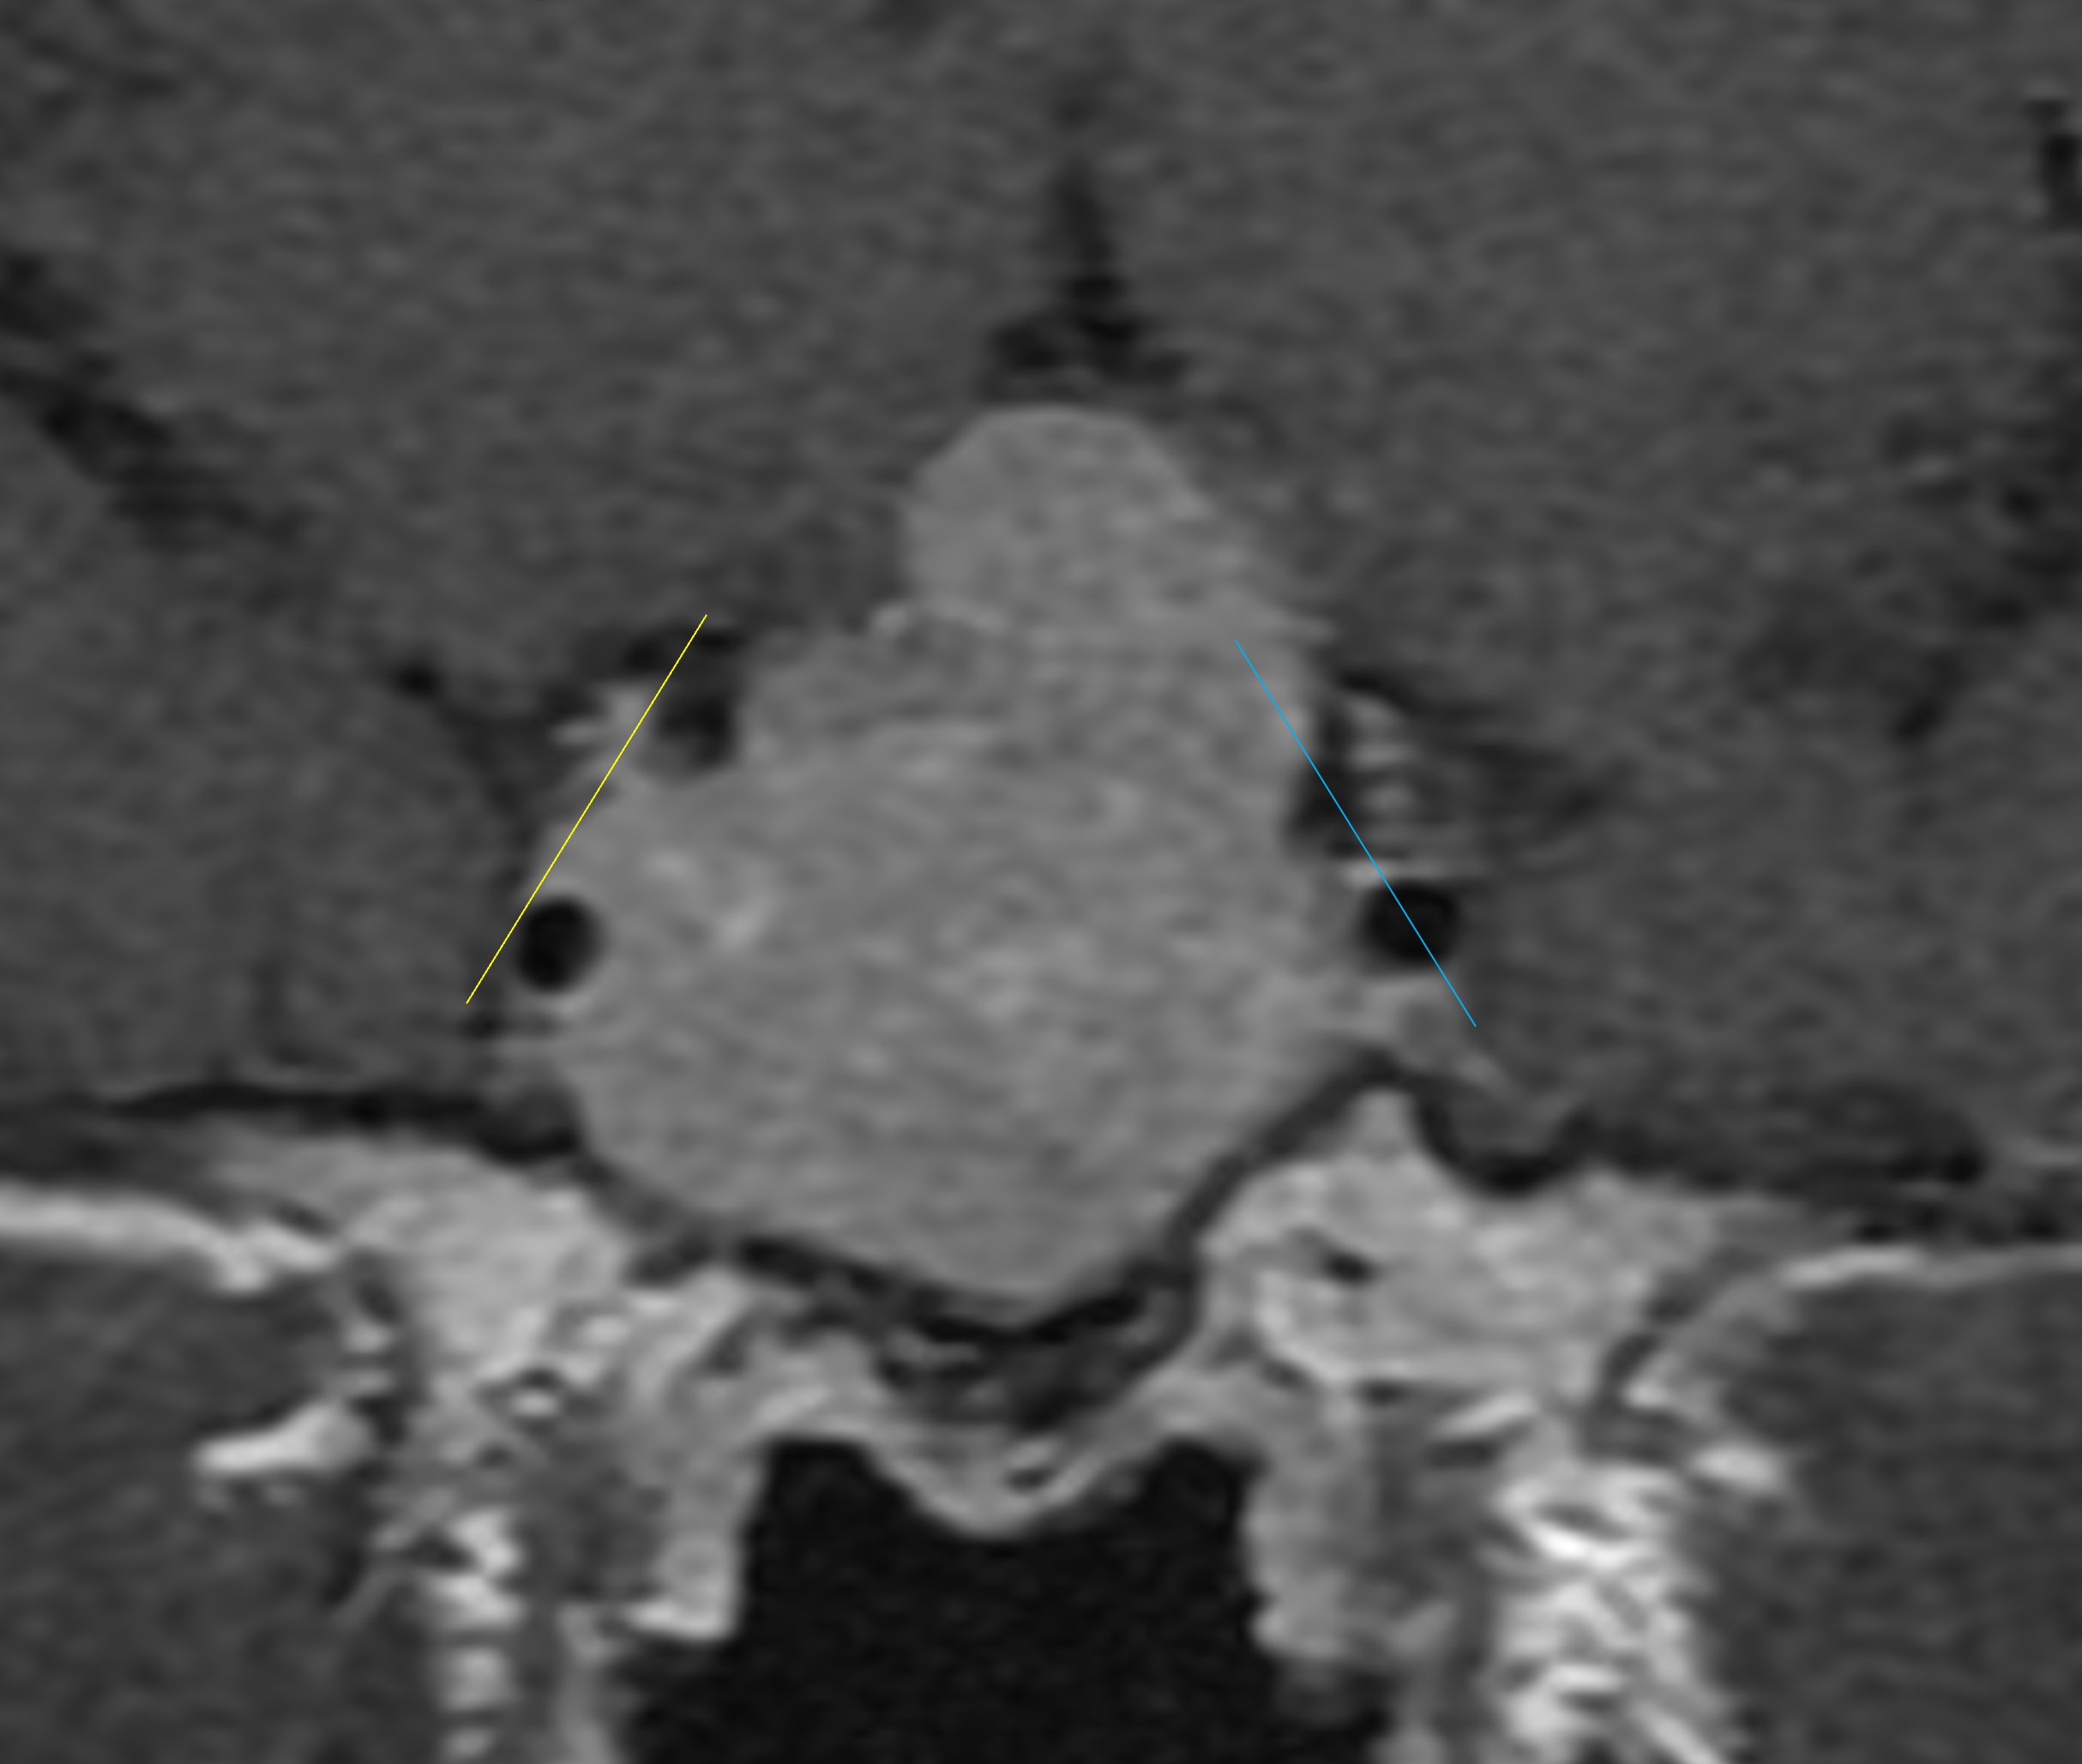

Age: 38

Sex: Male

Indication: Problems with vision

Pituitary macroadenoma